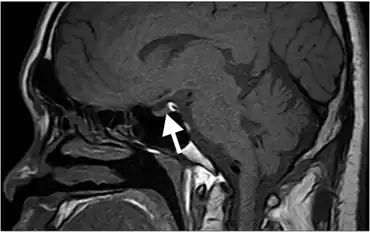

| Hyperintense signal of posterior pituitary on image could not be detected, lack of this bright spot is typical of central diabetes insipidus. | |